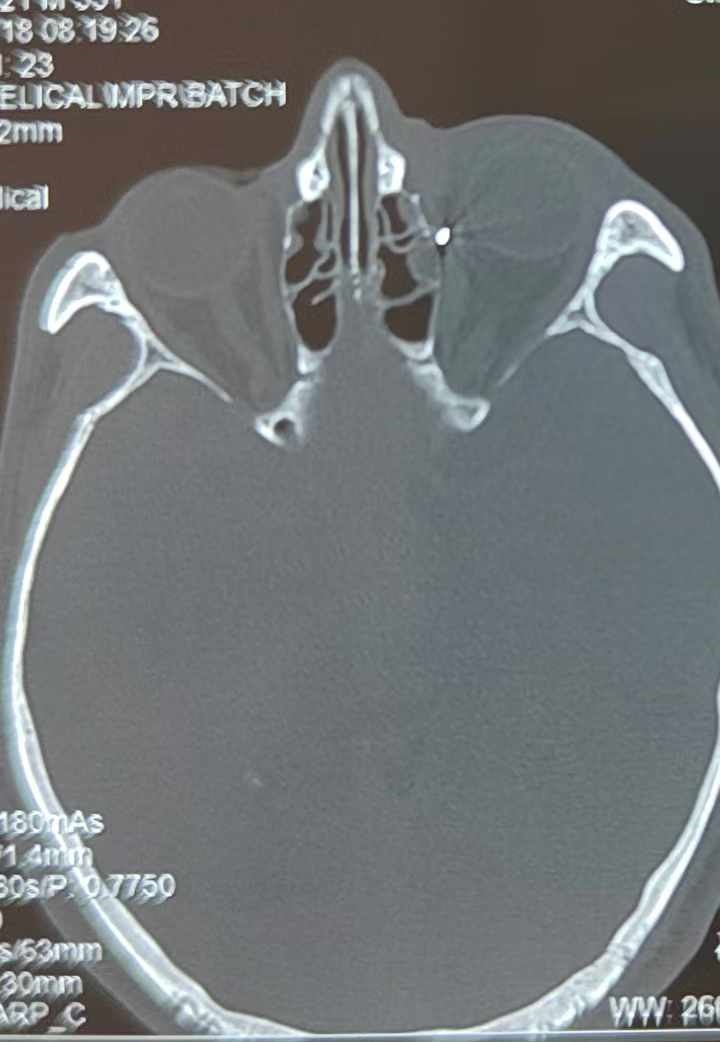

裝修工人高先生在作業(yè)過(guò)程中不慎被砸傷左眼,送至廈門(mén)眼科中心救治時(shí),眼外傷及眼底病2科副主任醫師李海波博士在CT檢查報告中發(fā)現,進(jìn)入眼內的異物在眶尖極為隱匿的位置,想要“不動(dòng)聲色”地取出來(lái),有些難度。

從CT報告中可以看出,高先生眼內的異物不是很大,但位于眼窩深處,緊鄰鼻骨,從CT影像判斷應該是金屬或合金異物。一般臨床上遇到這樣的情況,醫生會(huì )建議“保守觀(guān)察”,若異物傷及神經(jīng)、發(fā)生炎癥感染等,則需到條件較好、有眼眶病和眼外傷專(zhuān)業(yè)醫師的醫院進(jìn)行二期眶內異物取出術(shù)(2021年《中國眼眶異物診斷和治療專(zhuān)家共識》)。

李海波博士介紹,眶內異物想要通過(guò)手術(shù)取出,難度很大,一是因為位置隱匿,無(wú)法實(shí)現可視化操作;二是如果是磁性異物,現有手術(shù)工具磁性強度有限,很難吸出這么深的異物;三是可操作空間極為狹小,眶周軟組織多,異物周邊包裹緊密,像高先生這種情況,異物周邊還有很多神經(jīng)、血管,手術(shù)難度更高。

手術(shù)十分順利,李海波博士設計好了取出路徑,用這根細磁棒取出了一個(gè)米粒大小的鐵屑,過(guò)程中未造成二次傷害和大創(chuàng )面傷口。術(shù)后CT檢查顯示,高先生眼內再無(wú)異物,他此時(shí)才松了一口氣。